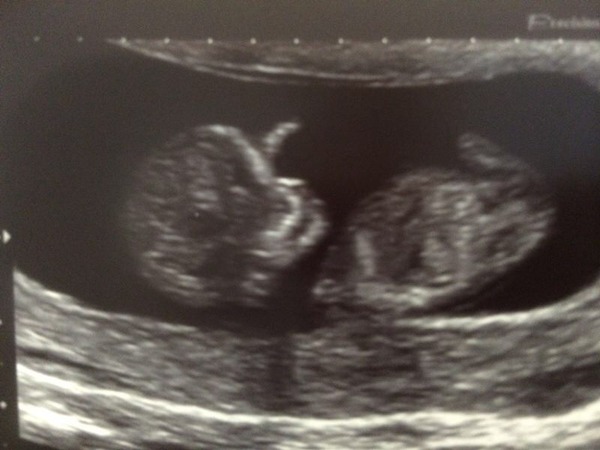

Hello from a waving babygiraffe! Due date now 5th July

Yey giraffe that's a cracking scan photo!

Great scan pic Giraffe - congratulations.

All was well at the scan, baby wriggling around in there!

Apparently the chance of everything now being fine is 99.5%, pretty happy with those odds!

10+0 today Smile